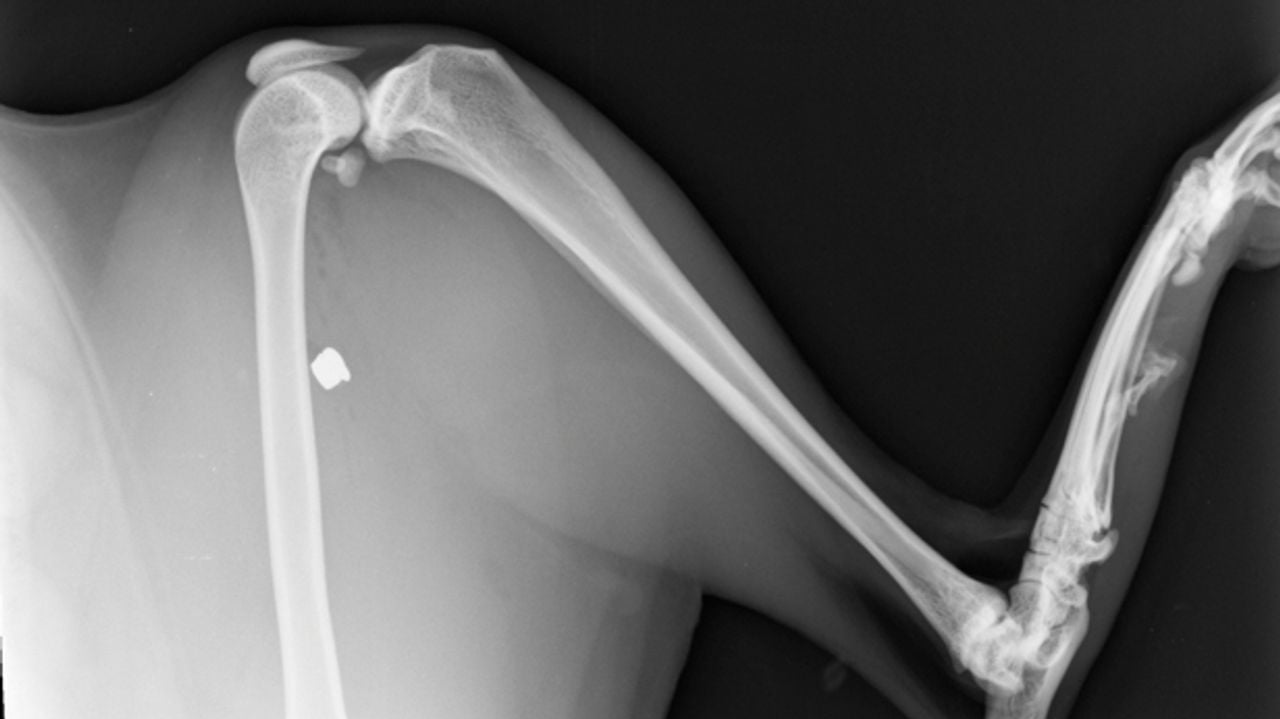

Daar aangekomen zag ze Simba hinken. "Ze had veel bloed aan haar achterpoot, bij haar dijbeen. We zijn meteen met haar naar een dierenarts gegaan. Er zat echt een gaatje in haar achterpoot. De dierenarts heeft er een foto van gemaakt. Het kogeltje zat vlak tegen het bot aan en Simba had ongelofelijk veel pijn. Vervolgens is ze geopereerd."

Het kogeltje is eruit gehaald en is afkomstig uit een luchtbuks. Het kogeltje is overgedragen aan de politie die de zaak onderzoekt.